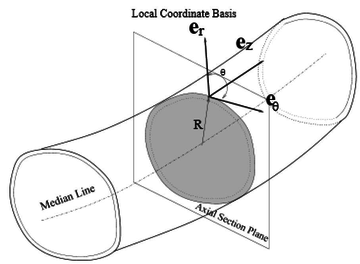

Boundary conditions from multiscale modeling of circulation: Another approach to impose the boundary conditions is to use reduced models, as 1D model or 0D (lumped) models. 1D and 0D models are mathematical models able to reproduce the systemic and pulmonary circulation. Figure 10 shows a standard approach to provide realistic local boundary conditions for 3D CFD simulations at the specific arterial domain using 1D models of the entire arterial tree and 0D models at the distal ends[83]. 1D model solves the Navier-Stokes equations under some assumptions (see appendix 9) and lumped models (0D models) can be derived from electrical circuit analogies where blood flow is represented by the current and arterial pressure by the voltage. Usually the electrical components of these circuits are resistances, inductances and capacitors. Where resistances represent arterial and peripheral resistance that occur as a result of viscous dissipation inside the vessels, capacitors represent volume compliance of the vessels that allows them to store large amounts of blood, and inductors represent inertia of the blood[75]. The values of these electrical components can be estimated from physical data of the subject [84][85]. This approach is quite used because it is capable to account for the effect of local pathological conditions on the whole circulatory system, providing realistic boundary conditions for the 3D problem [75][79][86].

| Figure 10: Coupling of 0D heart model, with 1D model (Systemic Circulation), 3D model (patient-specific geometry) and 0D lumped models (terminal resistance) to perform a computational analysis |